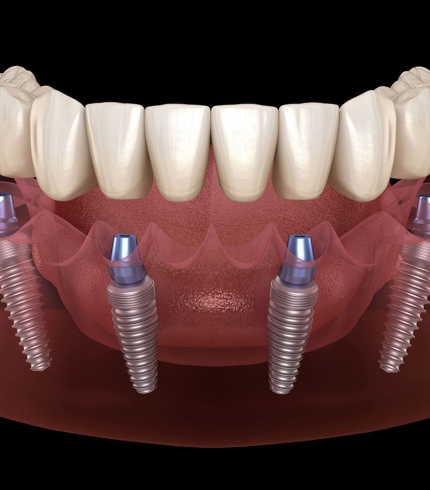

Çene Kisti Operasyonları yapılırken kist uygulanabiliyorsa tek parça halinde alınmaya çalışılır. Büyük ölçekli kistler önce küçültülür daha sonra cerrahi işlemle alınır. Çene kistleri çene kemiğinde ya da diş köklerinde bulanabilir. Eğer kist diş köklerindeyse operasyon sırasında kist ile ilgili diş ağızda bırakıldıysa dişe kanal tedavisi uygulanır ya da operasyon sırasında diş çekildiyse daha sonra ilgili dişe implant tedavisi uygulanır. Operasyon sonrasında bu süreç hem cerrah hem de hasta tarafından dikkat edilmesi bir dönemdir.